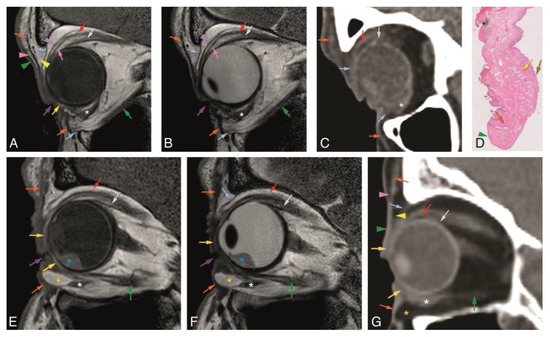

Figure 6. A–H: Patient #2 of Group 3 with a SCC of the skin of the right medial inferior eyelid. Comparison between a dedicated eyelid MRI protocol with a standard orbit MRI protocol and with histopathology. A–C: Dedicated eyelid protocol with axials T1-WI (A), T2-WI (B) and contrast-enhanced T1-WI with fat signal suppression (C) at the level of the inferior eyelid, showing the tumor (blue dashed arrow) involving the medial corner of the eye, with dubious involvement of the inferior tarsal plate (yellow arrow). D–F: Standard orbit protocol with axials T1-WI (D), T2-WI (E), and contrast-enhanced T1-WI with fat signal suppression (F) at the level of the inferior eyelid. Notice the much more difficult identification of the inferior tarsal plate (yellow arrow) and its relation with the tumor (blue dashed arrow). G and H: Histopathological examination H&E stain (0.5×) (G) and histopathological examination H&E stain (5×) (H). There was no slice available containing simultaneously the tumor and the tarsal plate and, therefore, it was difficult to evaluate tarsal invasion by the tumor. Notice that on (G), the left slice includes normal tarsal plate tissue (yellow arrow), but no tumor is seen, while the right slice shows the exophytic tumor (blue dashed arrow) arising from the skin but no tarsal plate tissue is seen. Skin cell proliferation compatible with good/moderately differentiated SCC (H). Blue dashed arrow: tumor; green arrowhead: skin; yellow arrow: tarsal plate; brown arrow: conjunctiva; orange arrowhead: eyelid margin.

In patient #2, initially, a MRI with a standard orbit protocol was performed, followed four days later by a MRI with a dedicated eyelid protocol (Figure 6). Both showed an enhancing lesion at the medial aspect of the inferior right eyelid. With the dedicated MRI protocol invasion of the inferior tarsal plate and medial palpebral ligament region was suspected (Figure 6A–C). The relation of the tumor with the inferior tarsal plate was much more difficult to assess with the standard orbit protocol (Figure 6D–F). The medial wall of the orbit was intact on MRI. Tumor excision was performed with direct defect closure. The final histopathological examination revealed a good/moderately differentiated squamous cell carcinoma of the skin of the eyelid, with free surgical excision margins. No perineural or angioinvasive extension was found (Figure 6G,H).